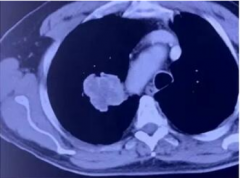

广州复大肿瘤医院冷冻疗法正规治肾癌获好评价

近日,广州复大肿瘤医院来了一位俄罗斯的老人家,患有肾癌肺转移,由于CT显示老人...